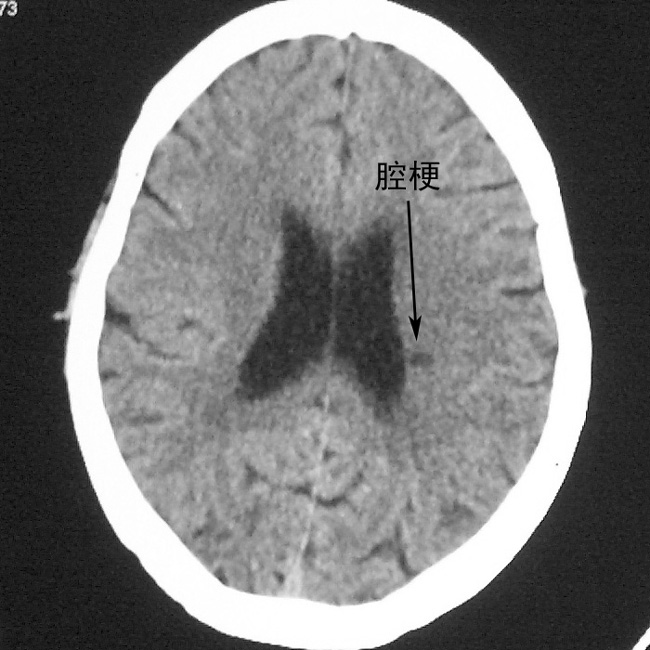

f,70y,口角歪斜、流涎、吐词不清三天

双侧多发腔梗

腔梗

1、右侧基底,左侧半卵圆中心腔梗。2脑萎缩。

左侧腔隙性梗塞灶,脑萎缩。

双侧多发腔梗 脑萎缩